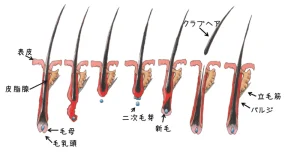

こんにちは、植毛医の内田直宏です。 移植床作成は植毛手術において採取作業と同等に最も大切な作業の1つです。 そもそも「移植床」や「ドナー」、「レシピエント」など、よく触れる言葉かと思いますが、それらが具体的に何を指してい […]